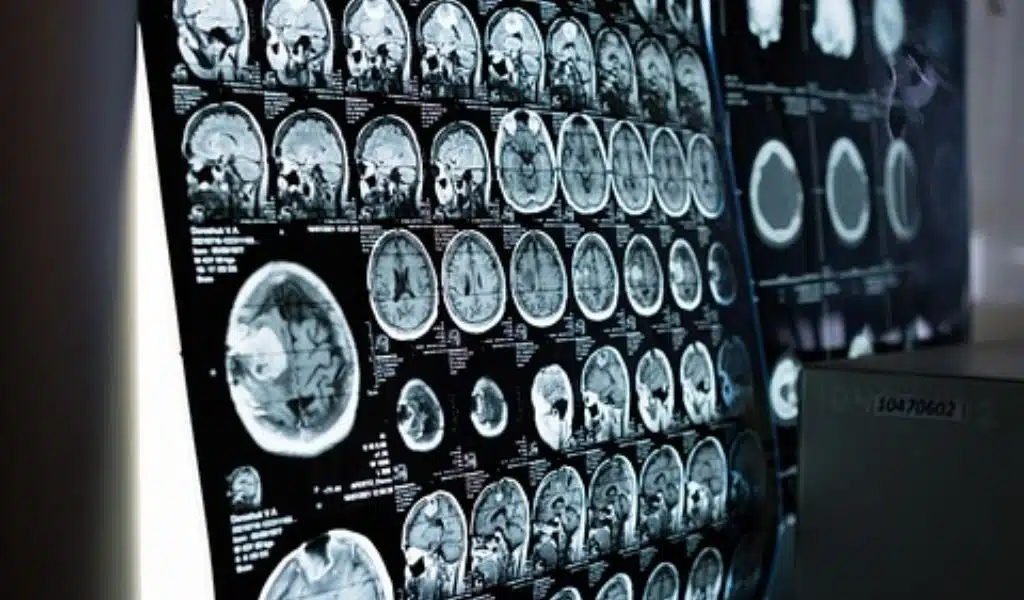

Anybody who has undergone an MRI or fMRI scan will attest to how noisy it is; when electric currents swirl, a strong magnetic field is created, resulting in a thorough scan of your brain. On this occasion, though, I was given a pair of specialized earbuds that started playing clips from The Wizard of Oz audiobook. Despite this, I could only just make out the loud cranking of the mechanical magnets.

Huth volunteered to participate in the study and spent more than 20 hours inside an fMRI scanner listening to audio samples as the device took precise images of his brain.